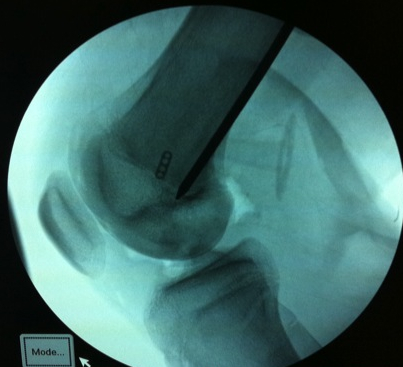

Femoral attachment

- 4 mm proximal and posterior to medial epicondyle

- image intensifier: intersection of the posterior femoral condyle with Blumensaat's line

- 40o anterior to avoid notch

- 40o proximal to avoid PCL tunnel

Tibial attachment

- 6 cm from joint line

- just posterior to pes attachment